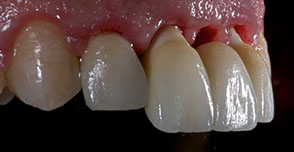

Fig. 12-13-14: Every demanding aesthetic treatment involving implants should have a provisional phase before the definitive prosthesis is delivered. It is mandatory to design natural emergence profiles before finishing the treatment.

7) Managing provisionals in implants in the aesthetic zone. Current concepts.

During the provisional phase of the treatment, a correct and natural emergence profile should be created following the adjacent tooth.